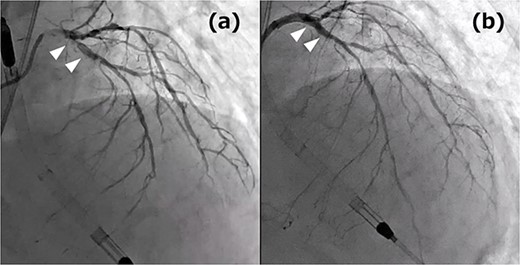

A 76-year-old male patient visited the emergency room with complaints of chest pain at rest. Upon hospital arrival, the patient was in cardiogenic shock (blood pressure: 68/48 mmHg, heart rate: 96 bpm). His blood samples showed elevated troponin I (5345.6 pg/ml) and a 12-lead electrocardiogram (ECG) revealed an ST-elevation in lead aVR. Therefore, the patient was diagnosed with ST-elevation myocardial infarction (STEMI), and emergency coronary angiography revealed severe stenosis of the left main coronary artery (LMCA). At that point, Impella CP (Abiomed, Danvers, MA, United States) was introduced from the left femoral artery. Subsequently, severe stenotic lesions were identified in the left anterior descending artery (LAD), the left circumflex artery, and the right coronary artery, and the patient was diagnosed with severe triple-vessel disease. Percutaneous coronary intervention (PCI) was performed only on the LMCA to LAD (Fig. 1), which appeared to be the culprit lesion and the 12-lead ECG revealed ST changes improvement. No other lesions were touched, and initial treatment ended at that point. However, other peripheral lesions remained, and transthoracic echocardiography revealed a remarkably reduced ejection fraction in this condition to 25%, thus revascularization of the remaining lesion was also considered essential. We maintained hemodynamics by continued circulatory support with Impella CP, and after improvement of general condition, we performed a standby elective coronary artery bypass graft (CABG) a week after the onset. CABG was performed with cardiopulmonary bypass without cardioplegic arrest (on-pump beating) and the graft design includes left internal thoracic artery-diagonal branch, great saphenous vein (SVG)–second diagonal branch–LAD, SVG-first obtuse marginal branch (OM)–second OM–atrioventricular node branch (Fig. 2). Impella CP was left to function as a left ventricular vent intraoperatively. We anastomosed the LAD by the SVG because it was a diffuse lesion with only a small area at the apex where anastomosis was possible, and we considered the perfusion area to be localized. The circulation of the patient became unstable on the first postoperative day; therefore, veno-arterial extracorporeal membrane oxygenation (ECMO) was introduced and he was managed with the so-called Ecpella (ECMO+Impella). The Impella CP was upgraded to Impella 5.5 from the right axillary artery on postoperative Day 4 because long-term Impella management was anticipated. Thereafter, his cardial function had gradually improved and he was weaned from ECMO on postoperative Day 6 and weaned from Impella 5.5 on postoperative Day 18. The patient’s general condition continued to improve gradually, and he was transferred to the hospital for continued rehabilitation on postoperative Day 68. One year after the operation, he is now doing well.

(a) Coronary angiography (CAG) before PCI: the white arrows indicate culprit lesions; (b) CAG post PCI: the white arrows indicate the treatment area.